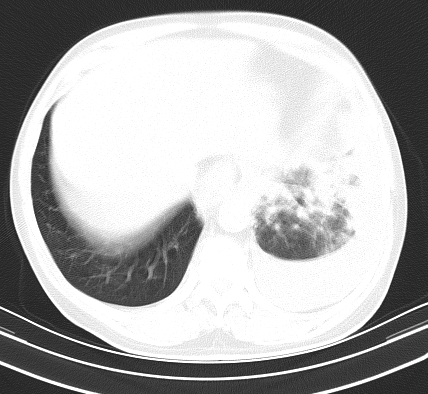

以下是引用老爱克斯新网客在2008-7-31 6:30:00的发言:[br]左肺上叶大片状病灶,左肺上叶支气管狭窄呈鼠尾状,左肺门增大,纵隔内见肿大淋巴结,左侧胸腔积液,余肺清晰。左肺中心型肺癌淋巴结转移,

以下是引用zjb在2008-7-31 6:32:00的发言:[br]左侧中心性肺癌 阻塞性肺炎 肺不张 胸腔积液 建议气管镜

以下是引用zjzjr在2008-7-31 8:45:00的发言:[br]考虑左侧中心性肺癌伴阻塞性肺炎,左肺上叶肺不张,纵隔淋巴结转移;左侧胸腔积液。建议行纤支镜检查。

以下是引用sdzyy在2008-7-31 8:47:00的发言:[br]病灶较治疗前有所进展,胸水增多, 左侧中心性肺癌 并 阻塞性肺炎 肺不张 胸腔积液 可能性大; 建议气管镜检查。 [br] [br]